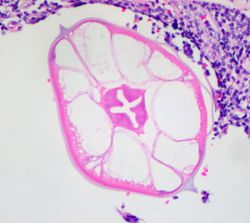

High magnification micrograph of a pinworm in cross section in the appendix. H&E stain.

Pinworms are sometimes diagnosed incidentally by pathology. Micrograph of male pinworm in cross section. Alae (blue arrow), intestine (red arrow) and testis (black arrow). H&E stain.